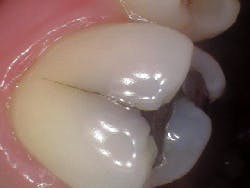

- Craze lines (figures 1 and 2)

Craze lines

- Most benign; visible fractures that only involve enamel

- Most adult teeth have craze lines; in the “posterior, they are usually evident crossing marginal ridges and extending along buccal and lingual surfaces”5

- Craze lines in the anterior are long and typically affect the enamel; are painless and of no concern beyond esthetics

- Occur naturally; increase in incidence with restorations or injury

- Challenge: It’s not always possible to tell if the fracture is limited to the enamel